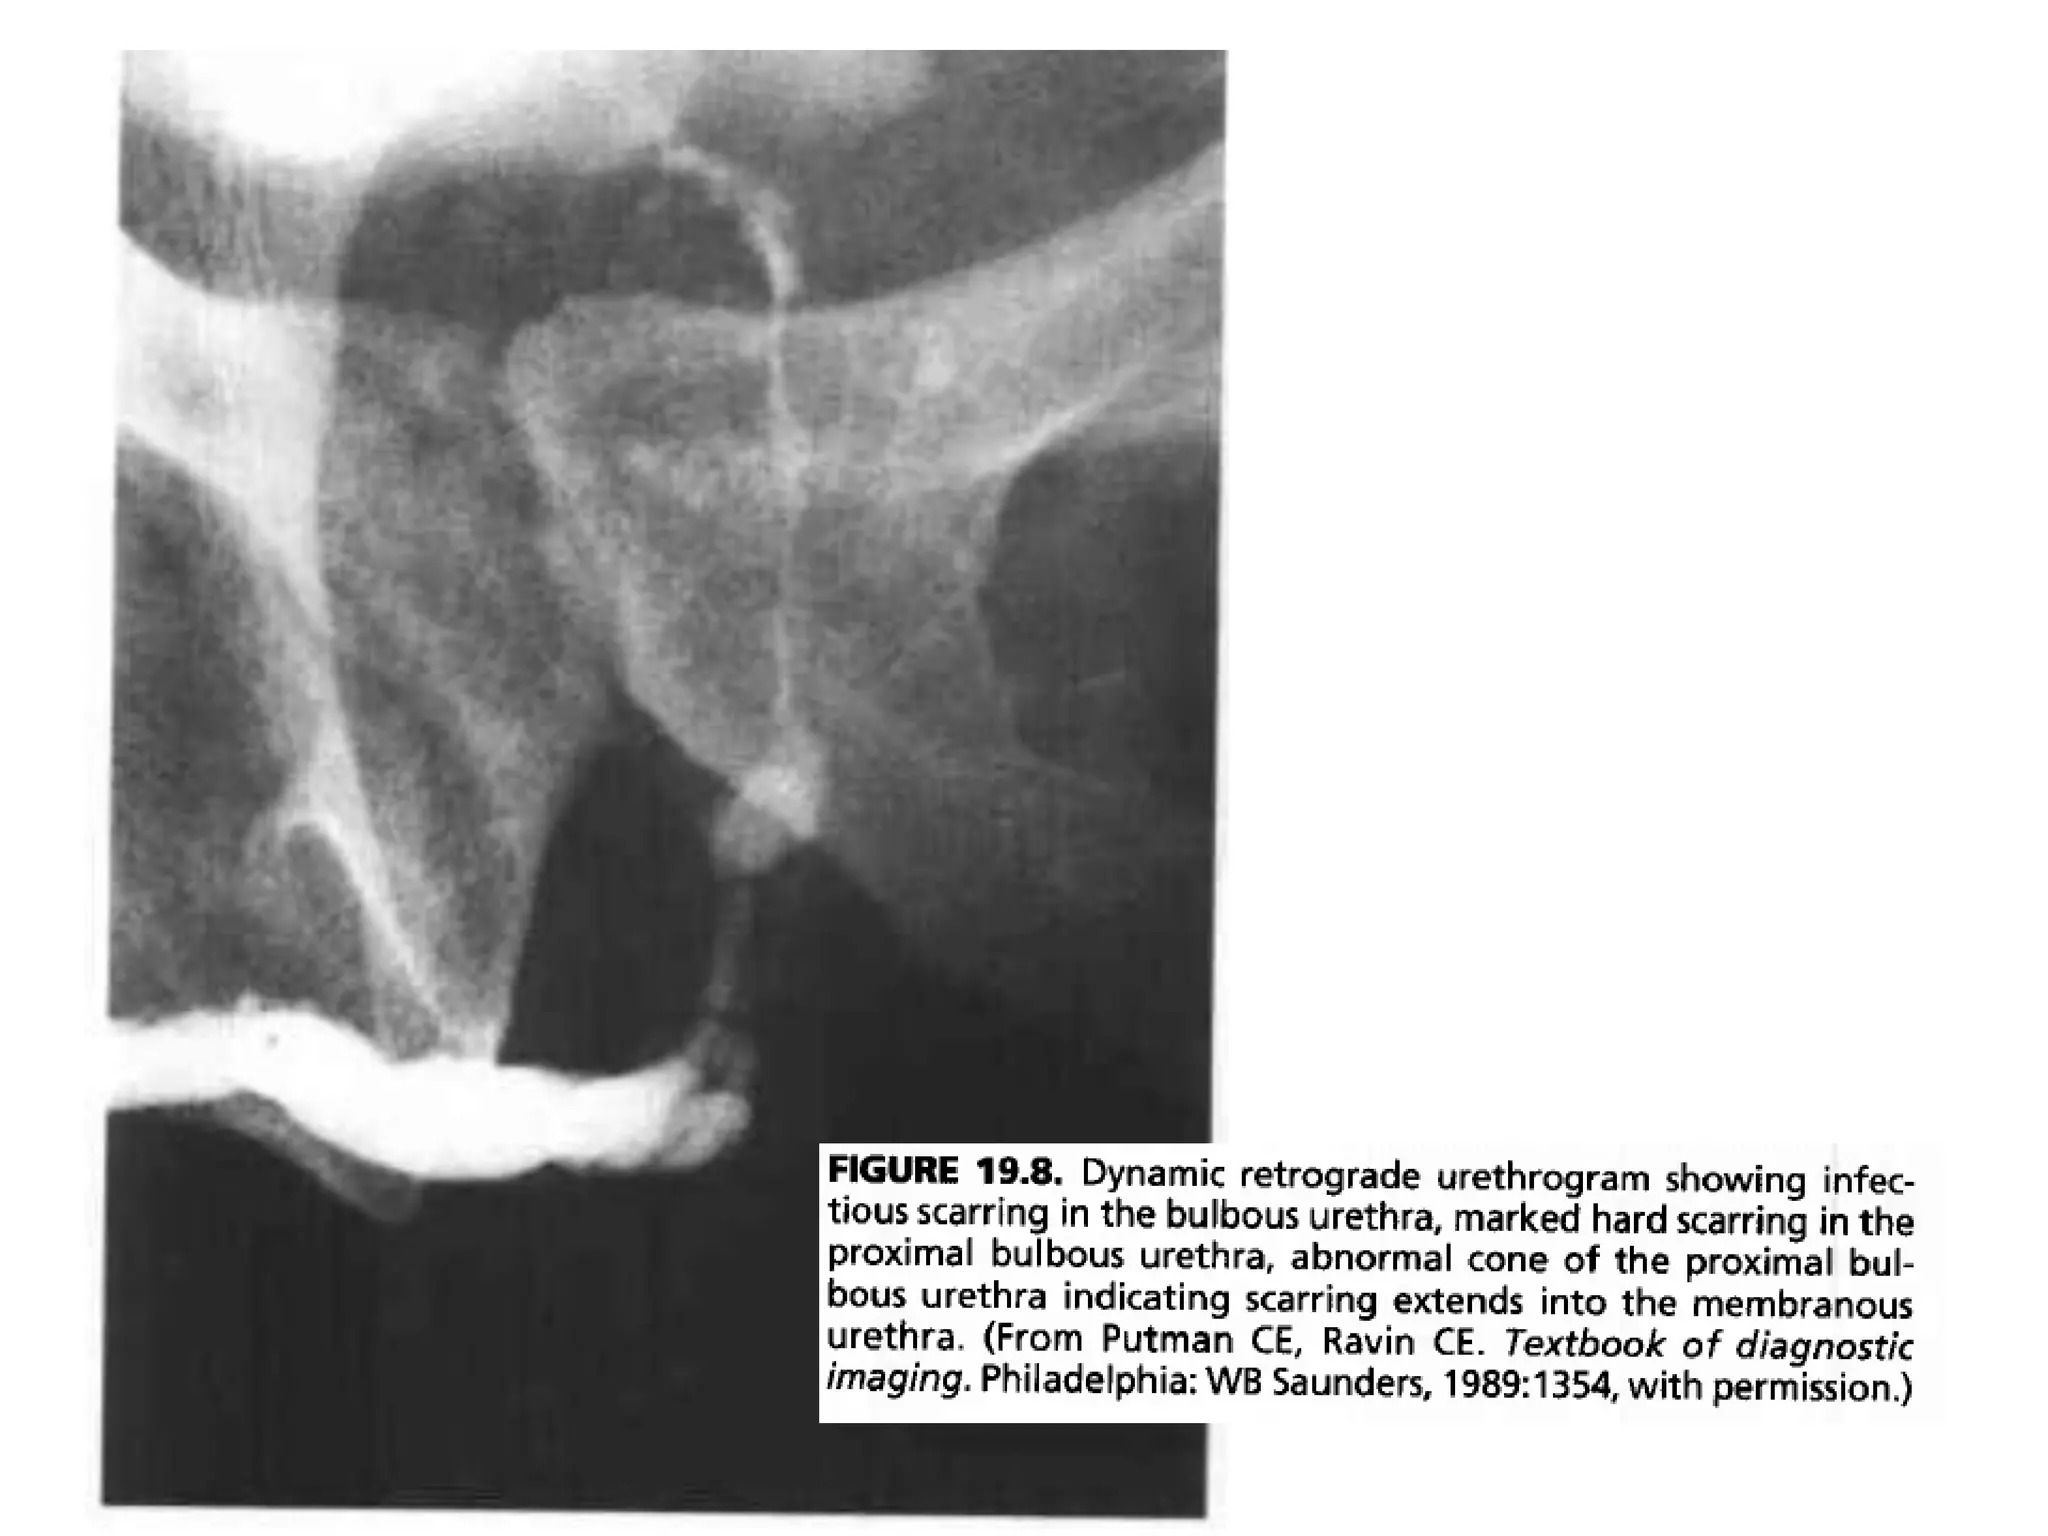

• If the disease has spread proximaly to the

membranous urethra, the normal cone shape of

the proximal bulbous urethra becomes

asymmetric and narrowed, giving an elongated

appearance to the membranous urethra.

• Abnormality of the normal convex cone shape of

the proximal bulbous urethra indicates scarring

extending into the membranous urethra.

• This radiologic finding is of prime importance to

the urologist, because surgical treatment may

involve cutting the scar tissue and consequently

the distal sphincter, which can result in iatrogenic

incontinence.